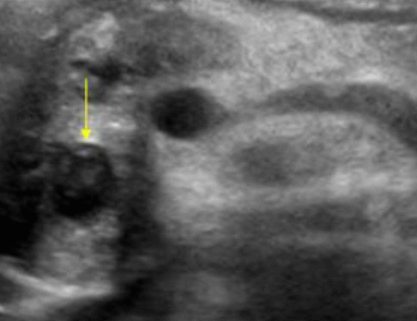

US finding

- 전반적으로 에코가 거칠게 보이는 간경변의 초음파소견과 비슷하여 주의가 필요함.

- 크기가 비슷한 고에코 또는 저에코 병변들이 보인다.

- 다중반사에 의한 comet-tail artifact를 보인다.